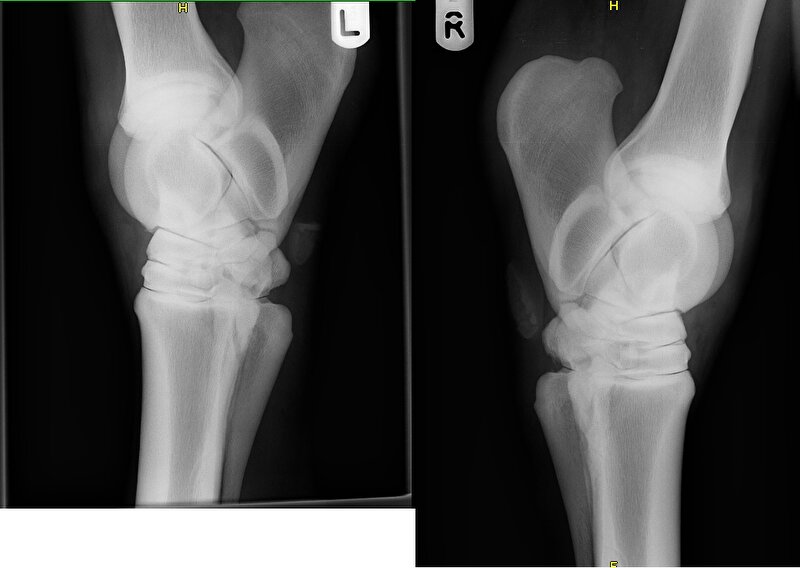

Vandaag de foto's opgehaald! :)

Kogelgewricht

Afbeelding

Spronggewricht

Nu woensdag maar afwachten.

Dierenarts vond haar in stap zuiver en in draf niet zozeer onregelmatig maar wat stijf. Ze zag de verdikking en gaf aan dat ze het logisch vond, dat ik dat uitgesloten wilde hebben. Allereerst foto's van het griffelbeentje. Prima in orde. Toen de pezen op de scan. Prima in orde. Het enige wat ze kon zien, was een verdikking van het weefsel, wat kan komen door een schop of ergens tegen aan stoten. Kortom blij dat, het uitgesloten is, alleen nog niets verder.